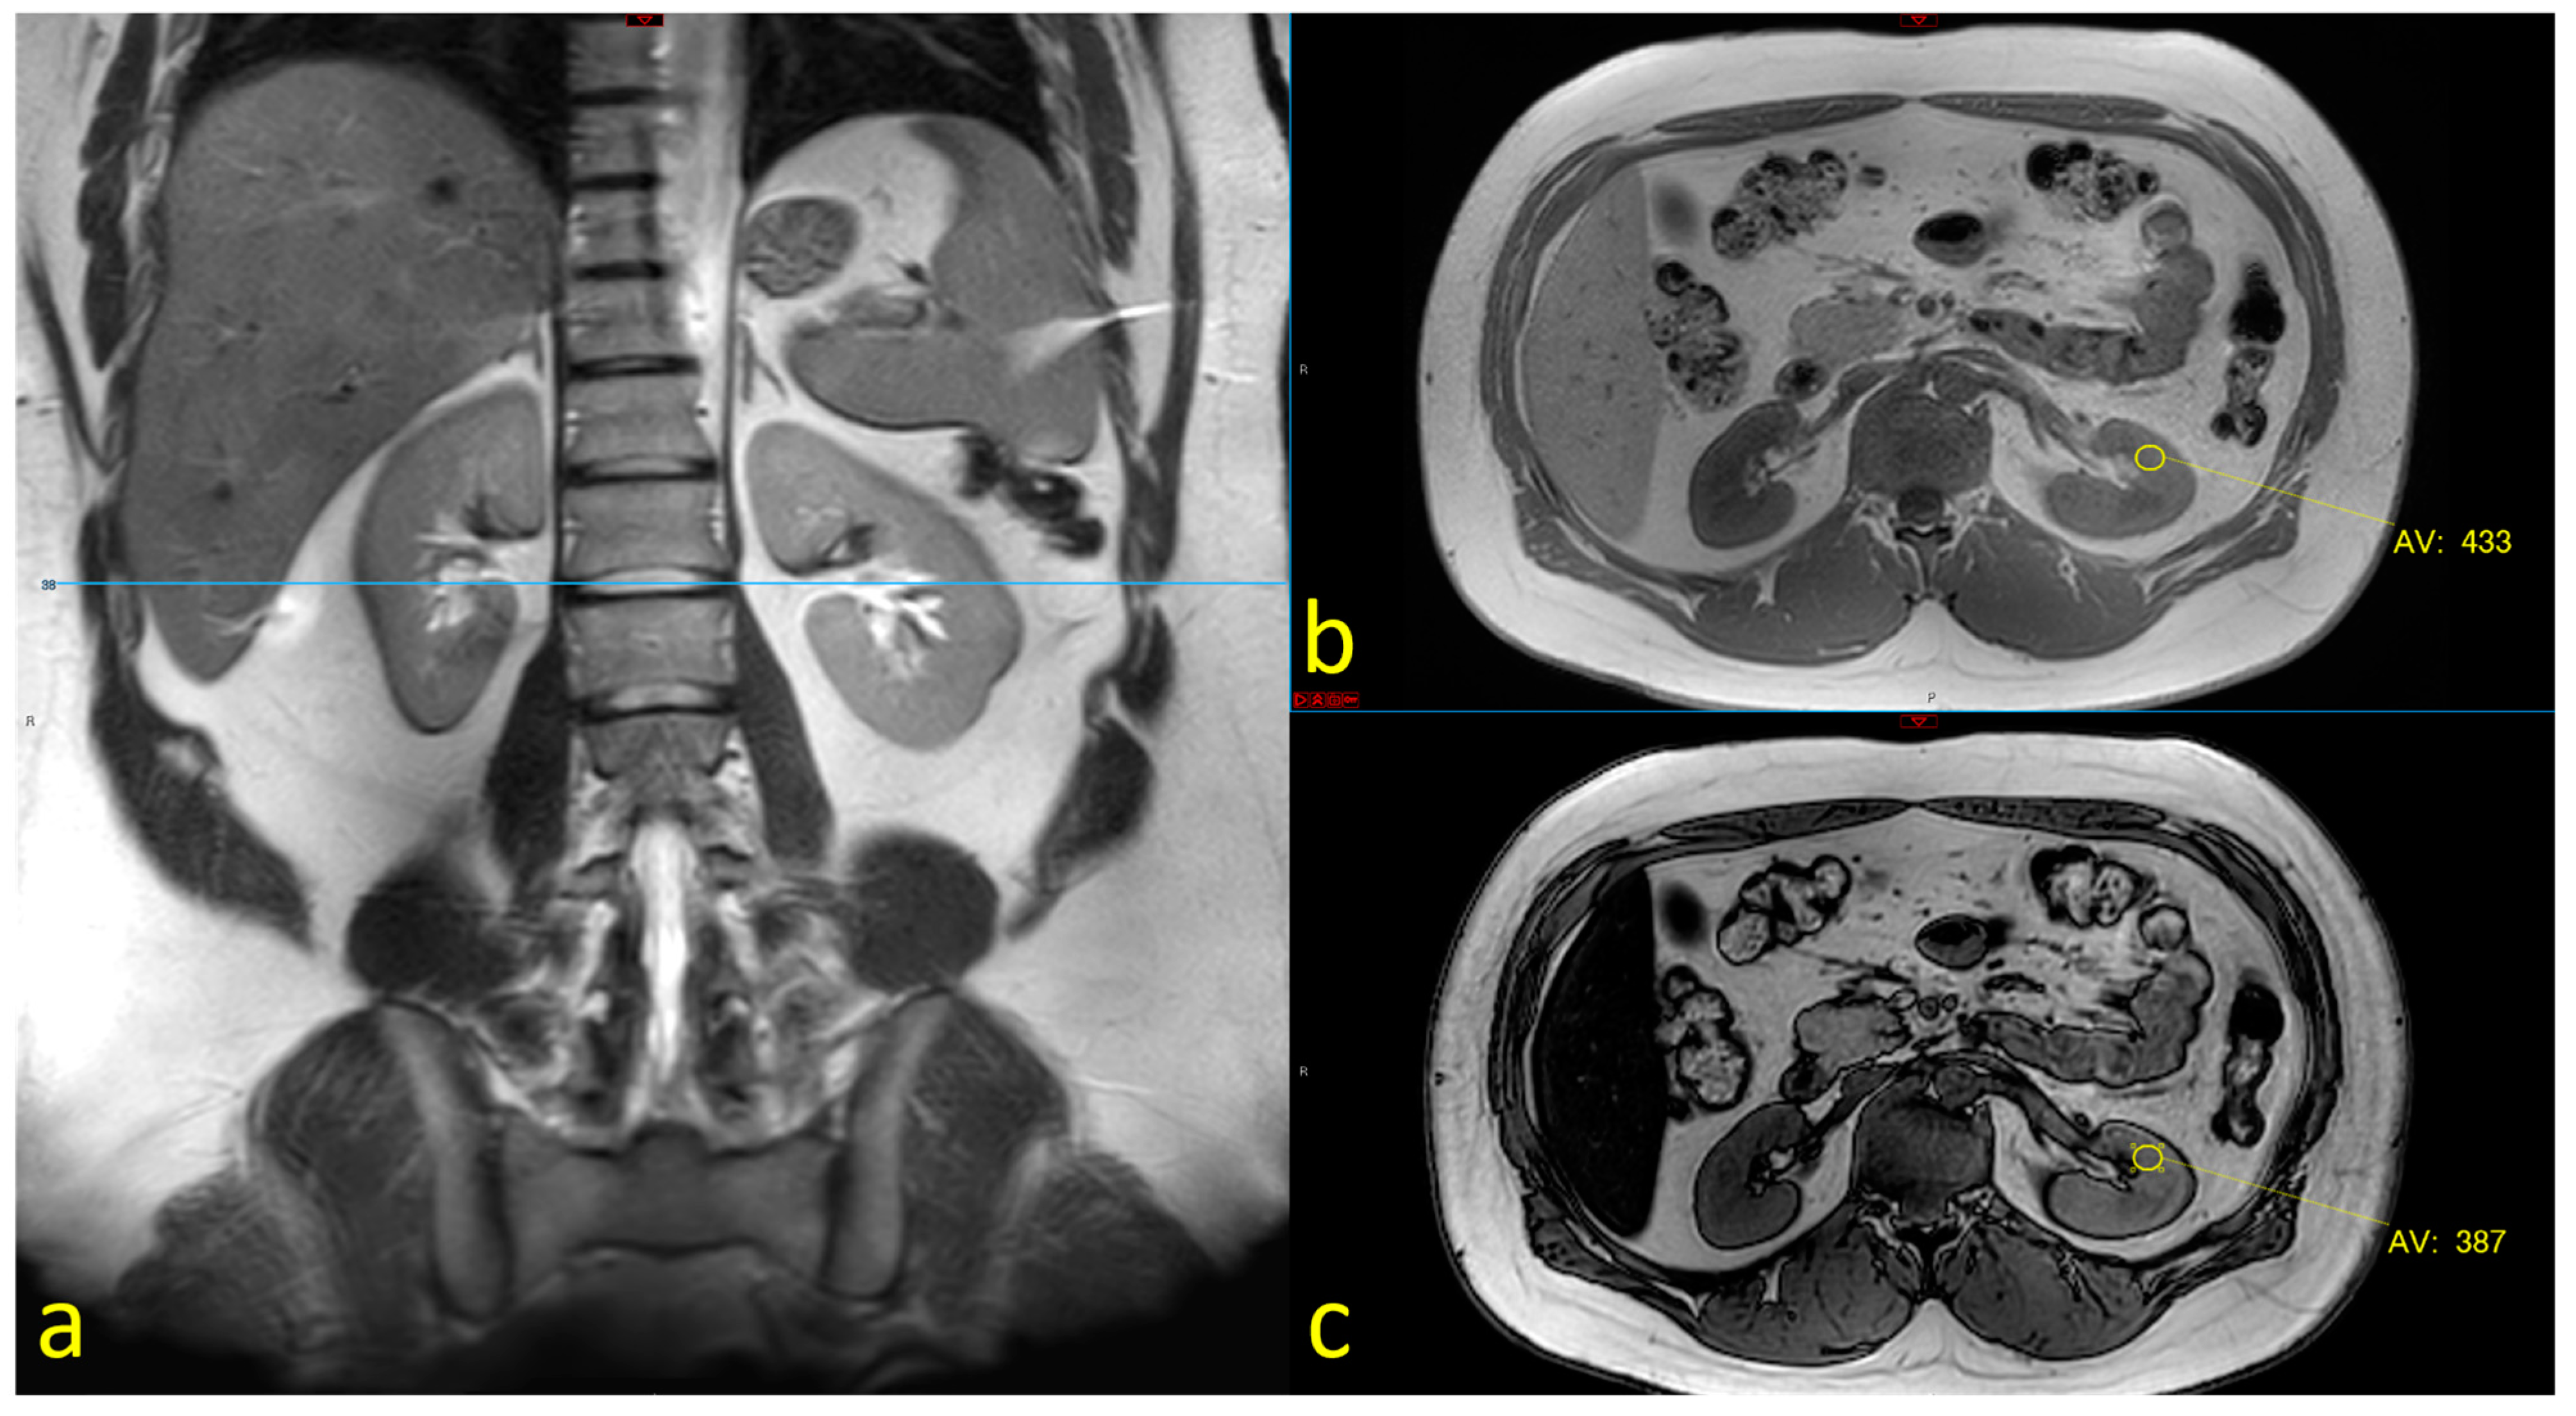

2.2. MRI Assessment